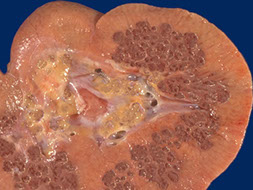

Autosomal Dominant Polycystic Kidney Disease (ADPKD)

- aka Adult Polycystic Kidney Disease

Multiple large bilateral cysts that destroys the parenchyma; the kidneys are HUGE